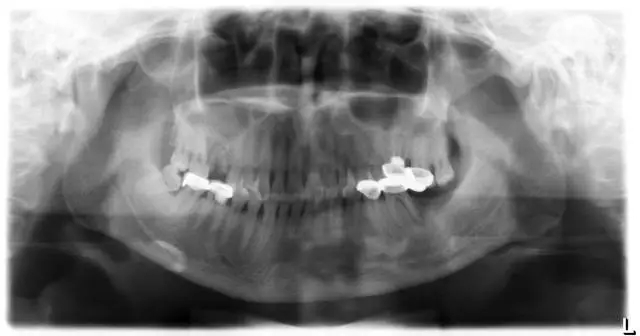

35、36、37烤瓷固定橋修復(fù),35、36為基牙,36烤瓷冠表面大量崩瓷,35探診(—),叩診(—),36探診(+),叩診(+)。

X線片顯示36已行治療,根充不徹底,遠中根牙周膜增寬,根尖周有暗影。

診斷:35、36、37不良修復(fù)體